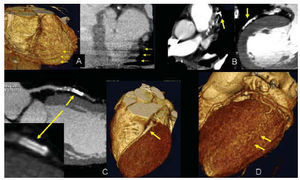

Dichas limitaciones se encuentran impuestas básicamente por una disminución en la calidad de la imagen a analizar, que puede reconocer las siguientes causas: artefactos de movimiento en relación con una apnea incorrecta, o debido a la reconstrucción en una fase del ciclo cardíaco inadecuada, o por extrasistolia frecuente; artefactos de imagen derivados de la presencia de lesiones intensamente calcificadas o de dispositivos vasculares implantados; calibre muy reducido del vaso en estudio (fig. 3 A-D).

Fig. 3. Limitaciones de los estudios por tomografía computarizada con detectores múltiples. A: artefacto de movimiento en una apnea incorrecta. En la reconstrucción 3D «renderizada» (izqda.) y en la proyección oblicua (dcha.) puede apreciarse el aspecto en «pila de monedas» (flechas amarillas) de los cortes inferiores debido al movimiento del diafragma. B: artefactos por clip vascular en un injerto coronario (izqda.) y marcada calcificación parietal de la arteria (dcha.) que limitan la visualización de la luz vascular. C: stent coronario. En la reconstrucción 3D «renderizadas» (dcha.) puede apreciarse claramente la presencia de un stent en el segmento proximal de la arteria descendente anterior (flecha amarilla); en la reconstrucción multiplanar (MPR) curva (izqda.) puede afirmarse la permeabilidad del stent al visualizarse la opacificación del vaso distal a éste, aunque no puede definirse la presencia de estenosis intra-stent debido a que el material del que está compuesto produce artefacto en la luz vascular, limitando su correcta visualización. D: vaso distal de pequeño tamaño. Reconstrucción 3D «renderizada» en la que puede apreciarse un arteria obtusa marginal de la circunfleja, de trayectoria tortuosa, con vaso distal de escaso tamaño sobre el que resulta difícil determinar la presencia de lesiones.